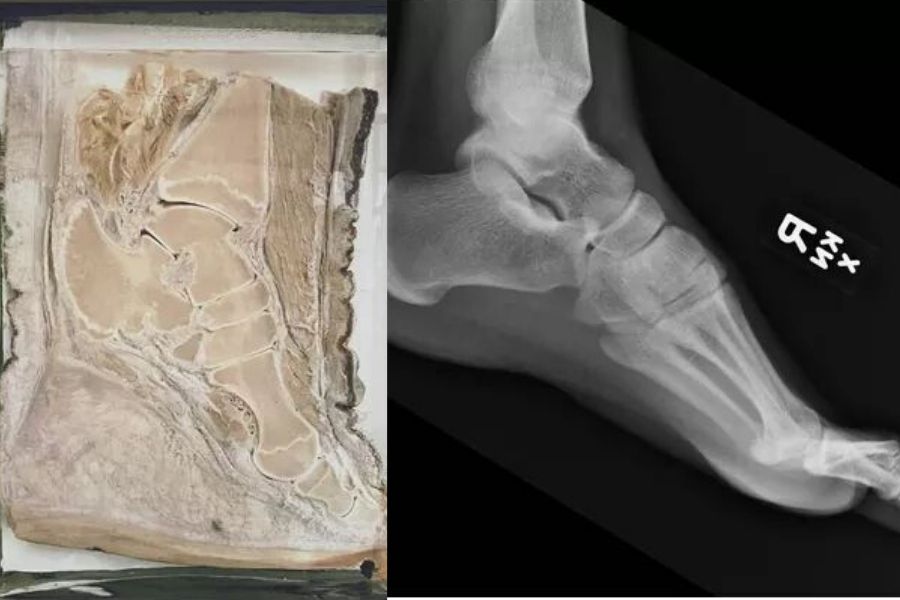

This Cross Section Of An Elephant’s Foot Next To A Human One Proves They Love Heels As Much As We Do

So are elephants just walking around on their tippy-toes all the time then?

Is the material in the rest of the foot just muscle, skin, and nail? Whatever it is, it’s one heck of a wedge heel.